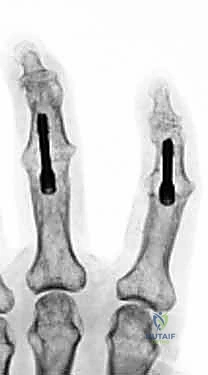

- Kirschner Wire (K-wire) Fixation:

- Advantages: Simplicity of technique, ready availability, low-cost implants. Historically, fusion rates up to 99% have been reported.

- Disadvantages: Less rigid fixation, often requiring additional external immobilization (splint/cast) which can lead to stiffness in surrounding joints. Higher risk of infection (superficial pin site, deep wound, osteomyelitis). Potential for pin migration. Minimal compression across the fusion site, which is biomechanically less favorable.